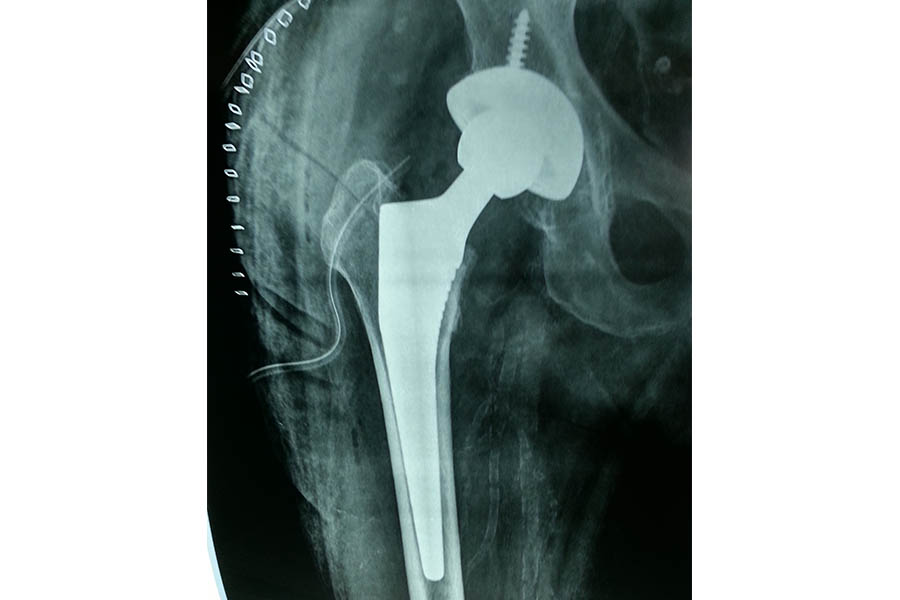

Total Hip Replacement

Case 1